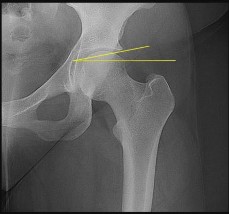

A 12-year-old male with a BMI > 95th percentile presents with hip pain and is diagnosed with a Slipped Capital Femoral Epiphysis (SCFE). Which of the following is the strongest indication for prophylactic in situ pinning of the asymptomatic contralateral hip?

Options:

Correct Answer: Underlying endocrinopathy, such as hypothyroidism

Explanation:

Prophylactic pinning of the contralateral hip in SCFE is controversial but is strongly indicated in patients with underlying endocrinopathies (e.g., hypothyroidism, growth hormone deficiency) or renal osteodystrophy. These conditions dramatically increase the risk of bilateral involvement. Other indications include inability to follow up, radiation therapy, and open triradiate cartilage (though age and triradiate status are debated, endocrinopathy is universally agreed upon).